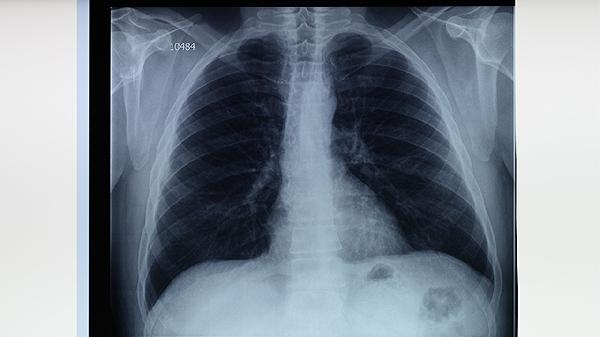

未接种卡介苗的家属应进行结核菌素试验,阴性者需补种疫苗。与病人密切接触的儿童、老年人等高风险人群可预防性服用异烟肼3个月。家属出现持续咳嗽两周以上需及时进行胸部X线检查。